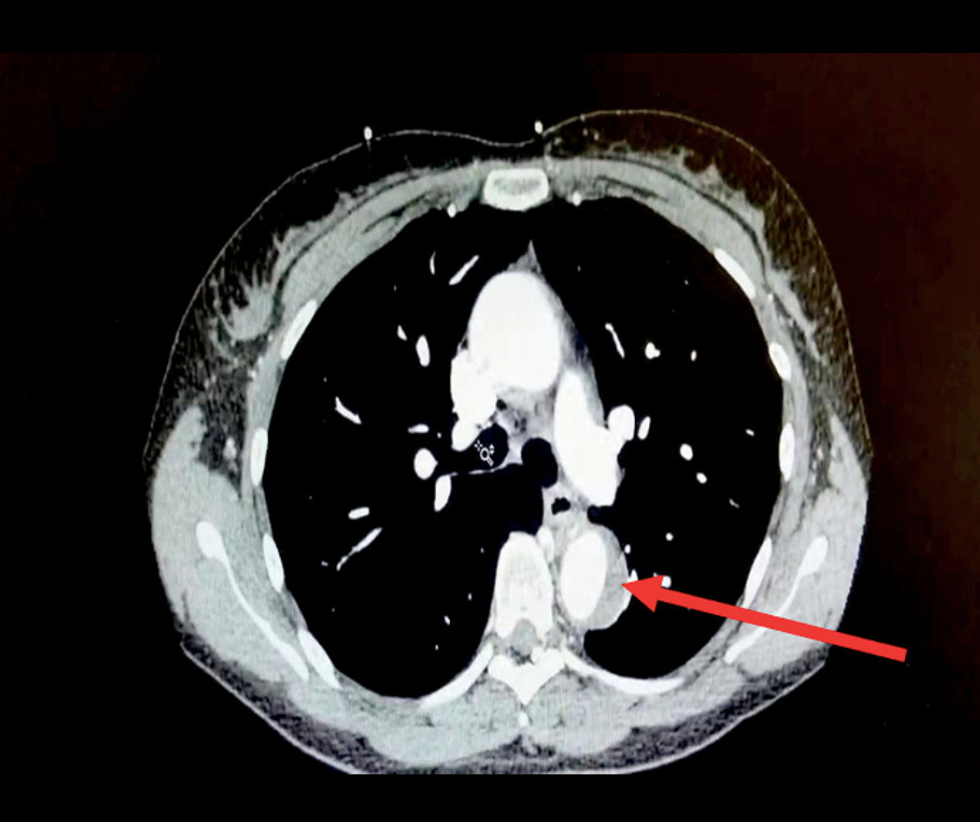

Medics gave the woman morphine and fentanyl to reduce the pain before confirming she had a leak in her aorta, the largest artery in the body which transports blood.

Medically known as an acute aortic syndrome or AAS, the disease can be severely life-threatening, reports the study. Men have a higher chance of developing AAS, and the peak age of diagnosis is later adulthood, around the age of 65.